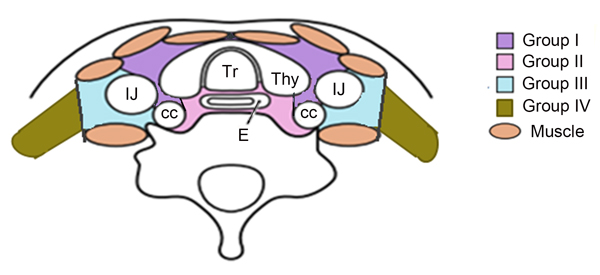

Figure 1: For the lower cervical region is divided into four sub-regions based on the Japan Esophageal Society (JES) and previous literature.

The mediastinal lymph node nomenclature is based on the new lymph node map published by the IASLC. [26] For the lower cervical region is divided into the left and right sides of the body midline, and each side was further divided into four subgroups based on the Japan Esophageal Society (JES) and Previous literature. [27-30] Subgroup I (No. 100 Superficial lymph nodes of the lower neck ): Cervical pretracheal lymph nodes located in the pretracheal fatty tissue, extending from the hyoid bone superiorly, to the left brachiocephalic vein inferiorly, including the prethyroidal lymph nodes and the prelaryngeal lymph nodes; subgroup II (No. 101 Cervical paraesophageal lymph nodes): Lymph nodes located around the cervical esophagus, including lymph nodes located along the recurrent laryngeal nerve and the cervical paratracheal lymph nodes. The lateral boundary is the medial border of the carotid sheath; subgroup III (No. 104 Lower cervical lymph nodes): Lymph nodes located in the lower cervical fossa, extending from the lower border of the cricoid cartilage superiorly, to the clavicle inferiorly, including the lower internal deep cervical lymph nodes, the medial boundary is the medial border of the carotid sheath; subgroup IV (Posterior cervical lymph nodes level): Lymph nodes extending from lower margin of the cricoid cartilage to the upper border of the manubrium, posterior edge of the sternocleidomastoid. The anatomic diagrammatic sketch of the lower cervical nodes region is shown in Figure 1.